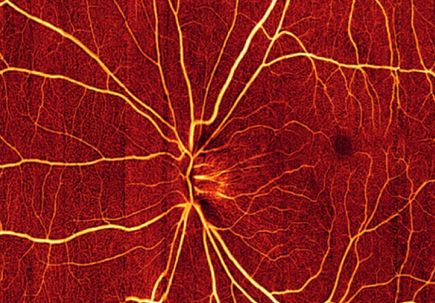

A non-invasive imaging technology used to evaluate eye health has saved the U.S. government and patients billions of dollars, a new study reveals.

Medicare and its patients saved a combined $11.2 billion between 2008 and 2015 by using optical coherence tomography, also known as OCT, according to a paper published in the American Journal of Ophthalmology.

OCT is a quick scan that takes a few seconds to minutes. It shines invisible infrared light into the eye to form images. Unlike ordinary photography, OCT produces detailed cross-sectional images and can measure very thin layers inside the eye. OCT is used to monitor eye health and is particularly important in age-related macular degeneration, glaucoma and diabetic eye disease - the three leading causes of blindness.